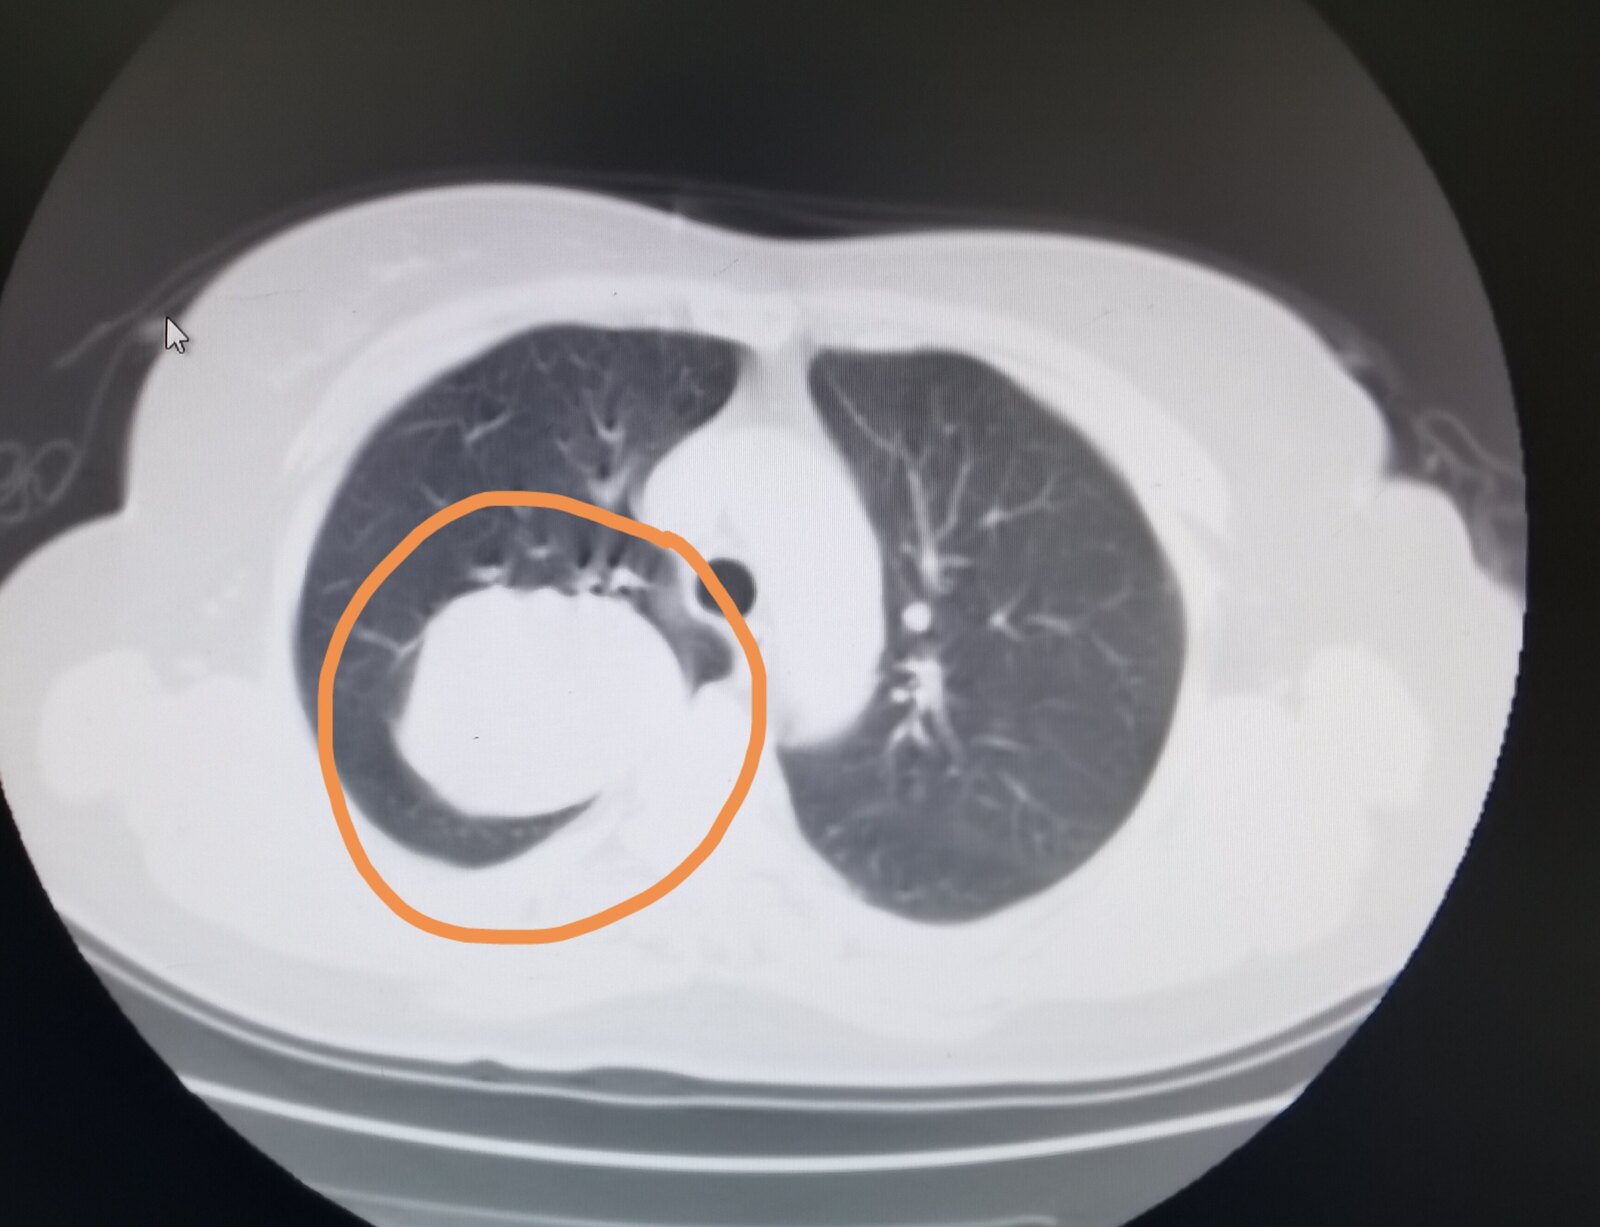

看图说肺囊泡性肺癌

图片尺寸700x676